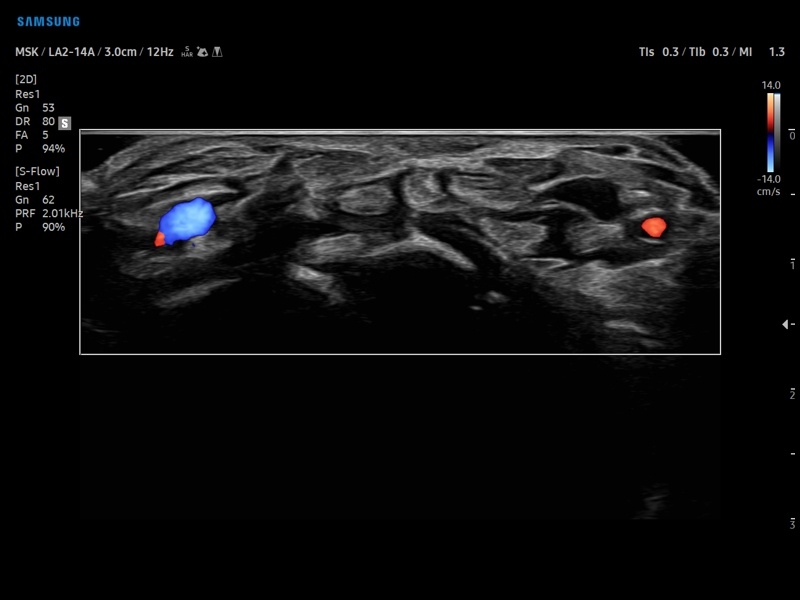

Ультразвуковой сканер V8-RUS является экспертным классом (премиальный уровень) и производится компанией Samsung Medison. Сканер V8 обеспечивает превосходное качество изображения благодаря использованию технологии Crystal Architecture™, которая включает в себя передовое аппаратное обеспечение, монокристальную технологию изготовления датчиков и сложную программную обработку ультразвуковых лучей.

• Цветной, энергетический и направленный энергетический допплер

• S-Detect для исследования молочной железы и щитовидной железы

• Расширенная сосудистая визуализация: Auto IMT+, 2D Arterial Analysis

• Диагностика костно-мышечной системы